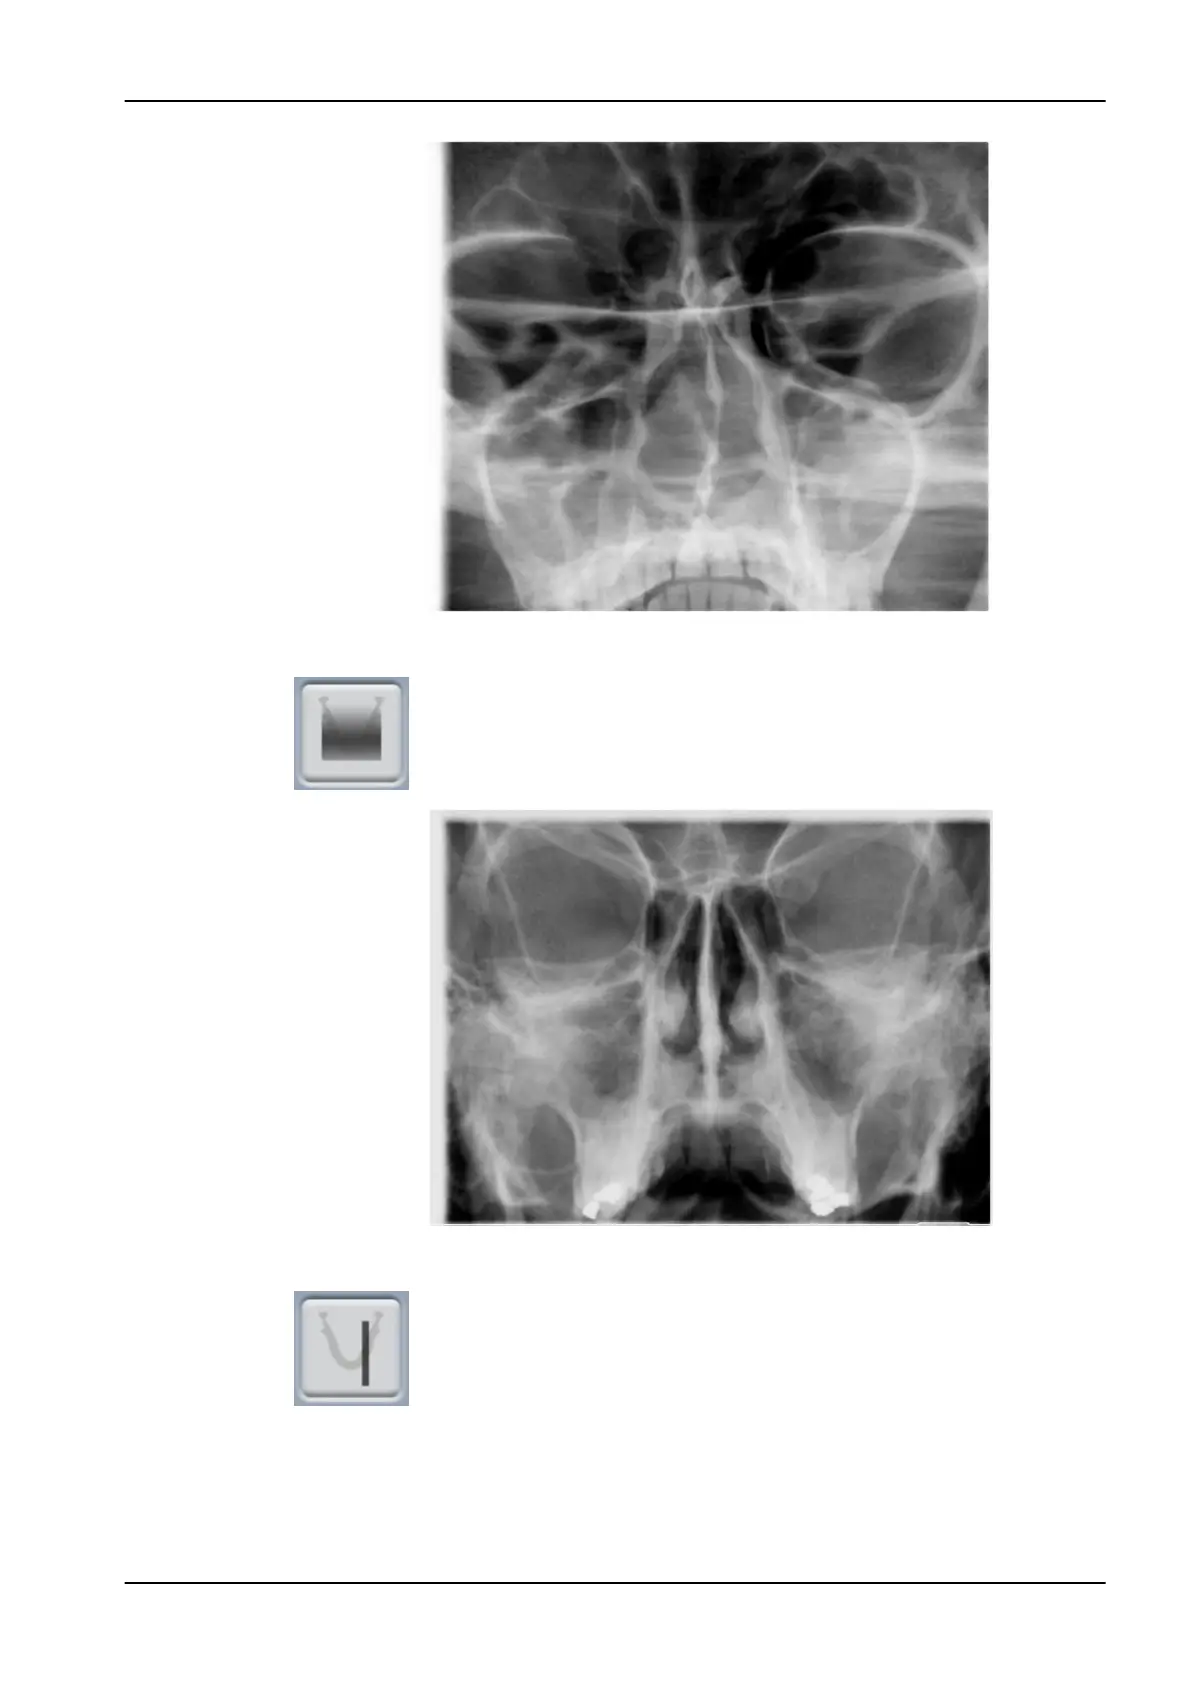

4.3.2 Posteroanterior linear

Posteroanterior linear sinus exposure.

4.3.3 Lateral

Lateral exposure of the left or right sinus area.